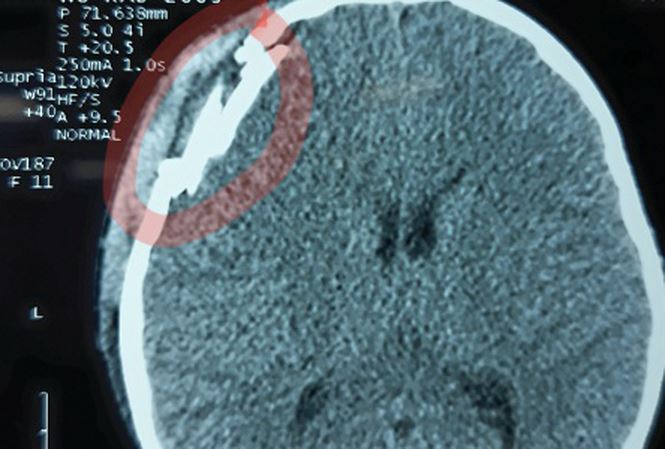

Cú đập mạnh vào đầu khiến cháu bé ngất xỉu, được người nhà đưa vào Bệnh viện Hữu nghị Việt Nam - Cu Ba Đồng Hới cấp cứu. Bé bị đau đầu, chóng mặt, buồn nôn, chảy máu mũi. Kết quả chụp phim CT scanner sọ não cho thấy bé bị chấn thương sọ não, vỡ xương sọ vùng trán phải, tụ máu ngoài màng cứng.